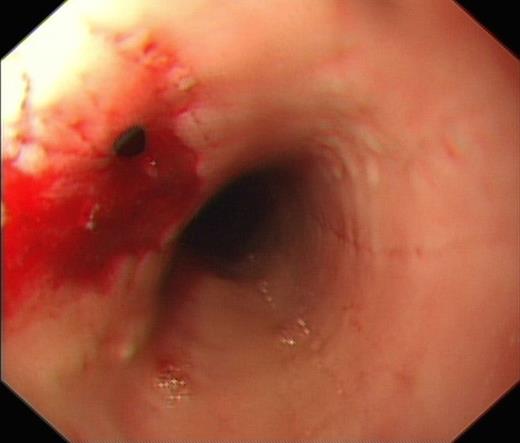

He subsequently underwent an Oesphago-gastro-duodenoscopy (OGD), which showed 2 separate oesophageal perforations, the first at 25cm from the incisors and the second at 27cm from the incisors. The perforation at 25cm was successfully clipped, however the second perforation at 27cm was deemed too big to clip (Fig. 1 & 2).

OGD showing clipped perforation at 25cm from incisors and further perforation at 27cm from incisors